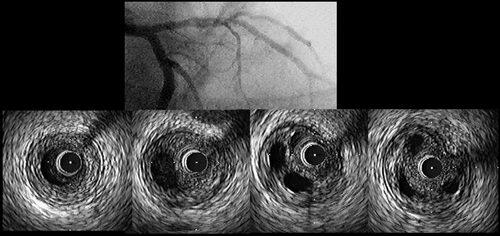

�Q�N�قǑO�ɓ��@�Ōo�������������������𗣂�IVUS���ł��B

LAD just��soft plaque�̒��ɁA�ۂ�����Ƌ��𗣍o�������܂��B

Zeta 3.5-18��direct stent���܂����Bslow flow�Ȃ���Z���I�����Ă��܂��B